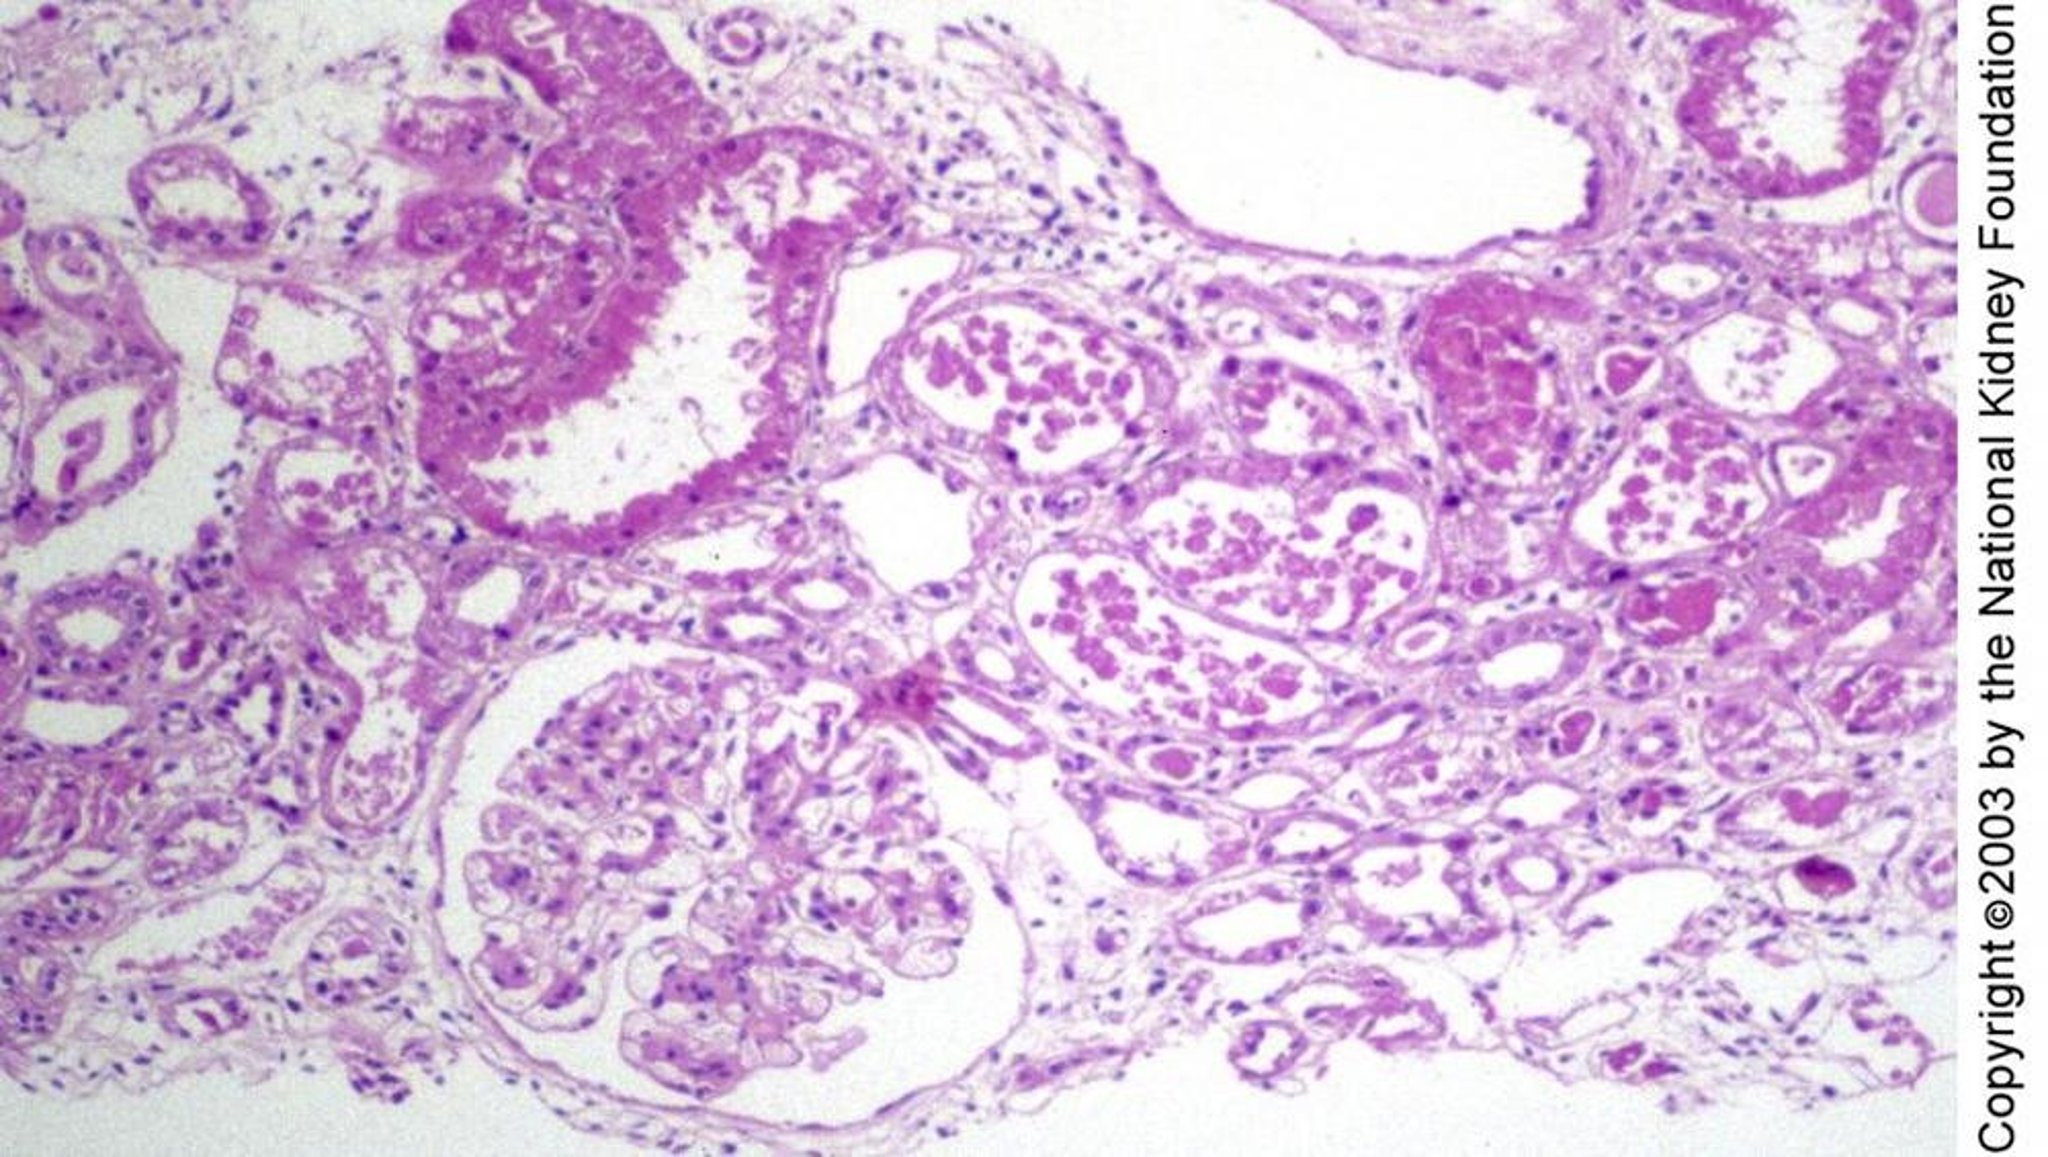

Acute Tubular Necrosis

Tubular injury in acute tubular necrosis may be manifest histologically as regenerating flattened tubular epithelium without necrosis, as seen to the right of the glomerulus, blebbing and individual cell degeneration, as in the top left, or frank necrosis, as in the middle of the image (periodic acid-Schiff stain, ×100).

Image provided by Agnes Fogo, MD, and the American Journal of Kidney Diseases' Atlas of Renal Pathology (see www.ajkd.org).